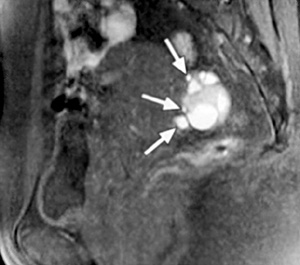

H μαγνητική τομογραφία (MRI) έχει αποδειχθεί ως ένα χρήσιμο μη επεμβατικό διαγνωστικό μέσο της ενδομητρίωσης. H μαγνητική τομογραφία υπερέχει της υπερηχογραφίας στην ενδομητρίωση του περιτοναίου, η οποία εμφανίζεται ως πολλαπλά μικρά οζίδια, γιατί μπορεί να ανιχνεύσει την ύπαρξη ενδομητριωσικών εμφυτεύσεων στις Τ1 ακολουθίες με ευαισθησία 11-27% και με σήμα το οποίο ποικίλει σε ένταση ανάλογα με την ενεργό δραστηριότητα και τη χρονική διάρκεια της βλάβης. Στις Τ2 ακολουθίες οι εμφυτεύσεις εμφανίζονται ως μάζες χαμηλού σήματος λόγω της αντιδραστικής ίνωσης που περιβάλλει τις μικρές συλλογές ενδομητριωσικού υλικού, αν και κάποιες φορές στο εσωτερικό των εμφυτεύσεων μπορεί να υπάρχει υψηλής έντασης σήμα λόγω της κυκλικής αιμορραγίας (εικόνα 2). Όταν όμως οι λήψεις της μαγνητικής τομογραφίας λαμβάνονται με καταστολή του λίπους, βελτιώνεται η ανίχνευση των ενδομητριωσικών εμφυτεύσεων στο περιτόναιο, αυξάνοντας την ευαισθησία της μεθόδου στο 47-61% και την ειδικότητα στο 87-97%.

Επιπλέον, στη μαγνητική τομογραφία οι συμφύσεις εμφανίζονται ως χαμηλής έντασης σήματος νηματοειδείς σχηματισμοί, οι οποίοι καθιστούν ασαφείς τις διαχωριστικές επιφάνειες δύο παρακείμενων οργάνων και μπορούν ενίοτε να προσλαμβάνουν σκιαστικό, χωρίς ωστόσο να αυξάνουν την ευαισθησία ή την ειδικότητα της μαγνητικής τομογραφίας. Σύμφωνα με μελέτη των Katayama και συν. εκτιμήθηκε η αξία της μαγνητικής τομογραφίας στην εκτίμηση των πυελικών συμφύσεων χρησιμοποιώντας μια ειδική τεχνική και διαπιστώθηκε πως η ευαισθησία και η ειδικότητα της μεθόδου είναι 72.5% και 87.4% αντίστοιχα. Η οπίσθια κλίση και καθήλωση της μήτρας στον δουγλάσειο, η προσκόλληση των ωοθηκών μεταξύ τους και στην οπίσθια επιφάνεια της μήτρας, η γωνίωση των εντερικών ελίκων, η ανύψωση των οπίσθιων κολπικών θόλων, η εγκυστωμένη συλλογή υγρού και η παρουσία υδροσαλπίγγων αποτελούν έμμεσα ευρήματα, ενδεικτικά συμφύσεων (εικόνα 3).(15,16)

Εικόνα 3. Πυελική ενδομητρίωση με σοβαρές συμφύσεις. Οβελιαία τομή με καταστολή του λίπους στην Τ1 ακολουθία (Α) και κλασική Τ2 οβελιαία τομή (Β), όπου απεικονίζονται πολλαπλές ενδομητριωσικές κύστεις στον δουγλάσειο. Μικρά ενδομητριώματα με υψηλής έντασης σήμα αναγνωρίζονται στην Τ1 ακολουθία με καταστολή του λίπους (βέλη στη τομή Α). Οπίσθια κλίση της μήτρας με ανύψωση του οπισθίου κολπικού θόλου (κεφαλή βέλους στη τομή Β), ενδεικτικά παρουσίας σοβαρών συμφύσεων στον δουγλάσειο. Επιπλέον διαπιστώνεται αδενομύωση στον ορογόνο της οπισθίας επιφάνειας του μυομητρίου (βέλη στην τομή Β).